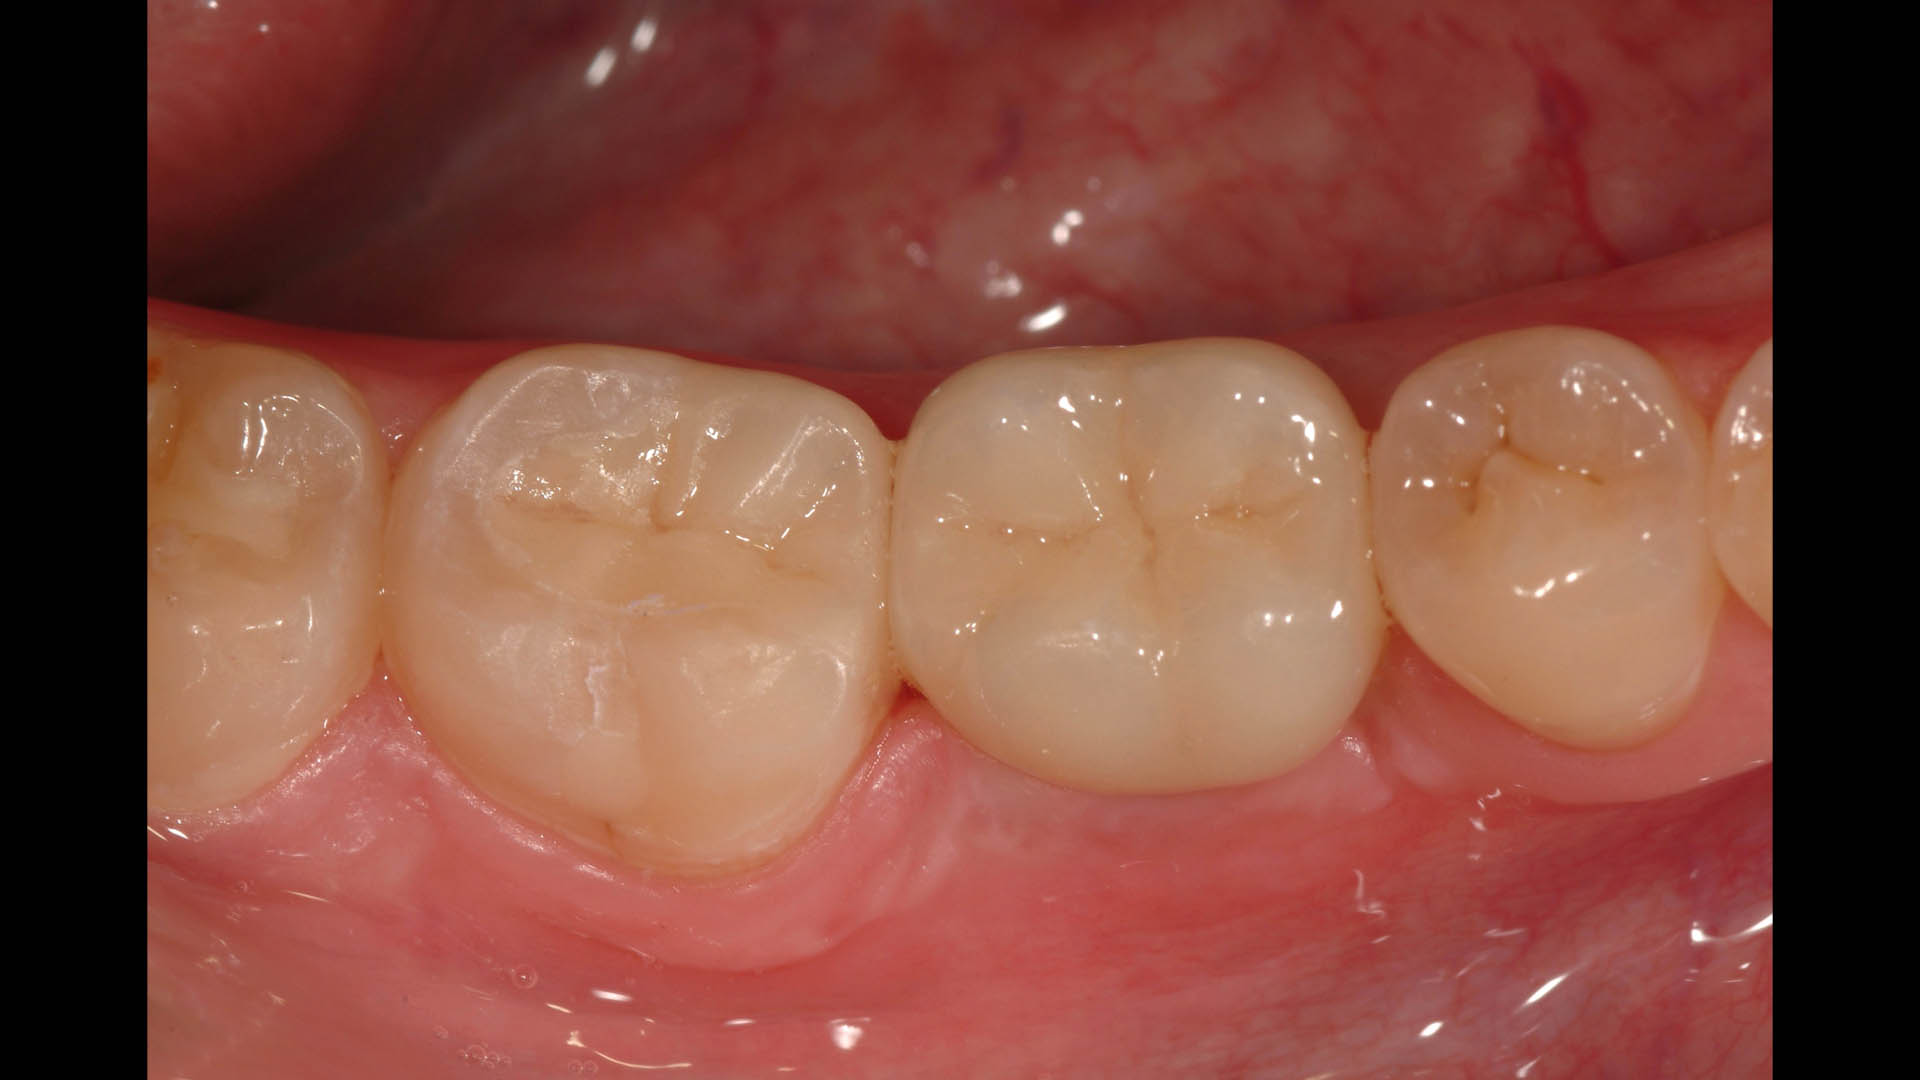

Take a glimpse into the magic of Coral Gables Dentistry through our before and after pictures. See firsthand the incredible smile makeover transformations that have brought confidence and joy to our patients.